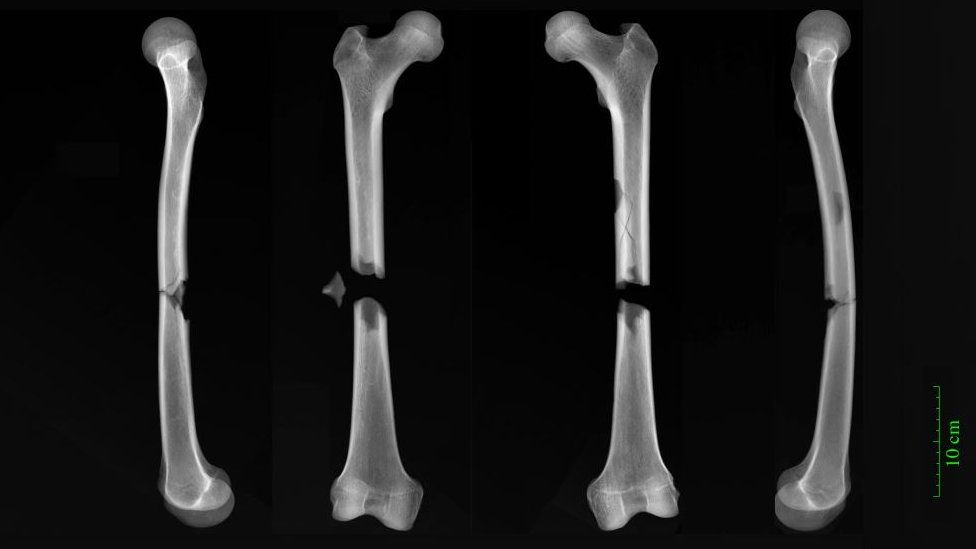

디트마 박사는 또다른 놀라운 사실은 중세 시대에 전쟁이 흔했는데도 죽은 사람들 사이에서 치유 여부와 관계없이 무기와 관련한 부상의 증거는 아직 없다고 말했다. 그렇다고 해서 폭력이 없었다는 뜻은 아니다. 실제로 연구진은 디트마 박사가 말한 살아남은 수도사의 유해가 도적 떼의 공격일 수 있으며 그가 둔탁한 물건으로 머리를 맞았다는 징후를 보였다고 보고했다. 디트마 박사는 “그는 무언가에 머리를 부딪쳤을 수도 있다. 하지만 팔에 남은 골절은 방어흔이므로 자신을 보호하기 위해 팔을 들어 올렸다는 것을 의미한다”고 설명했다. 반면 또 다른 수도사는 그리 운이 좋지 않았다. 그의 유골은 부러진 목과 다리를 보여주는 데 한 가지 가능성은 그가 수레에 치였을 가능성이 있다는 것이다. 디트마 박사는 “그가 입은 부상은 사람들이 허벅지 높이에서 차에 치일 때 경험하는 것과 가장 유사하다”면서 “우리는 그가 어떤 심각한 사고를 당했든 간에 그가 아마 사망했을 것이라고 말해도 무방하다고 생각한다”고 말했다.